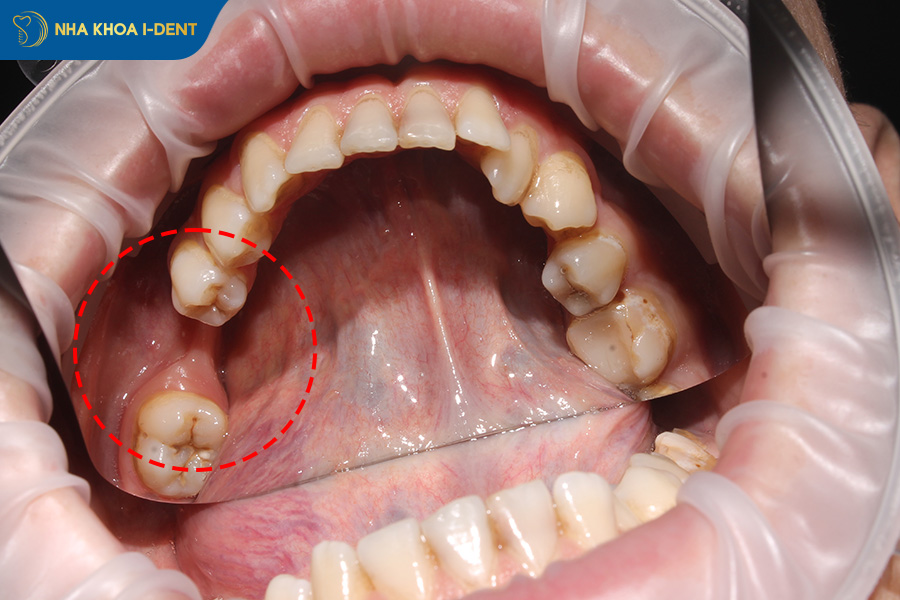

Tiêu xương hàm do mất răng cần hạn chế chỉnh nha hoặc phải ghép xương trước niềng